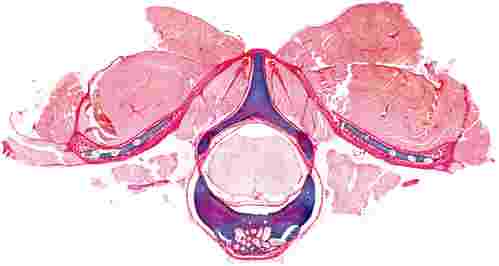

Best Image Award (Scientific Category)

Dr Rebecca Rolfe (Lead Author) and Ms Sarah Hennigan

Description

Transverse histological view of a thoracic vertebra from an embryonic chick, stained to show cartilage (blue) and collagen (red/ pink). Spinal ligaments are stained dark red positioned adjacent to muscle, symmetrically connecting rib cartilage to vertebral processes. This approach provides opportunity to examine the maturation of spinal tissues during development. |